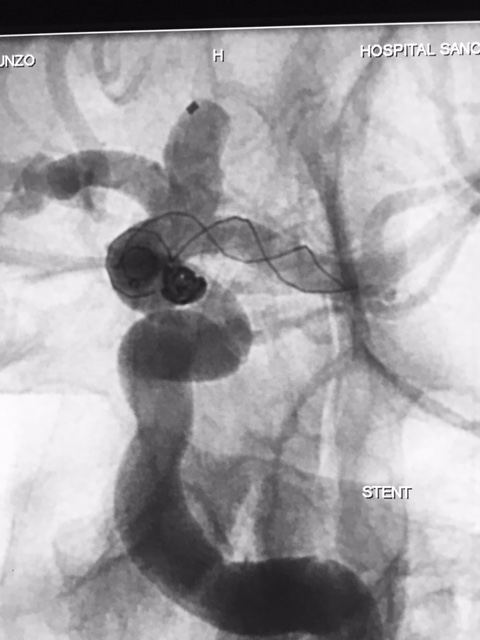

Ambos posicionados em segmento proximal de artéria carótida interna, com progressão gradativa no Cateter Envoy XB DA 070 para segmento petroso desta mesma artéria. Inicialmente realizou micronavegação  do  aneurisma de segmento comunicantecateter com microcateter Echelon 10 microguia Silver Speed 0,10  e liberado 2 microespiras  posteriormente progredindo até saco aneurismático do aneurisma de topo de carótida. Assim, em sistema coaxial foi progredido microcateter VASCO 21 até o segmento M1 da artéria cerebral média, sendo optado pela orientação do aneurisma e orientação de seu colo com maior envolvimento deste mesmo vaso. Assim, diante do posicionamento adequado de ambos os microcateteres iniciou a liberação controlado do stent LEO, e por seguinte liberado um total de 8 microespiras no saco aneurismático até oclusão completa-Raymond 1.